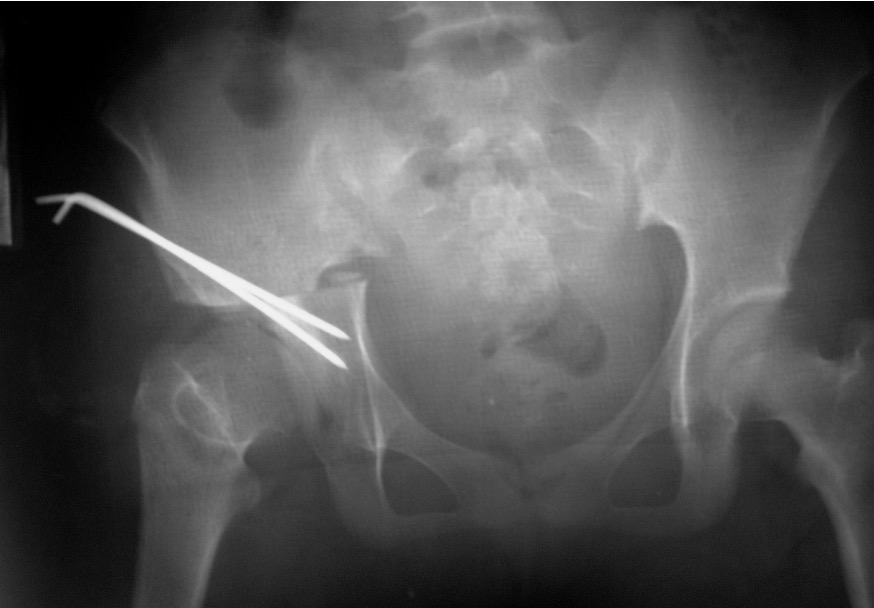

Xray

Dislocated hips in the setting of DDH with ncreased acetabular index

Osteotomy

- through greater sciatic notch to between ASIS and AIIS

- Gigli saw passed around greater sciatic notch

- osteotomy posterior to anterior

- acetabulum rotated anteriorly and laterally